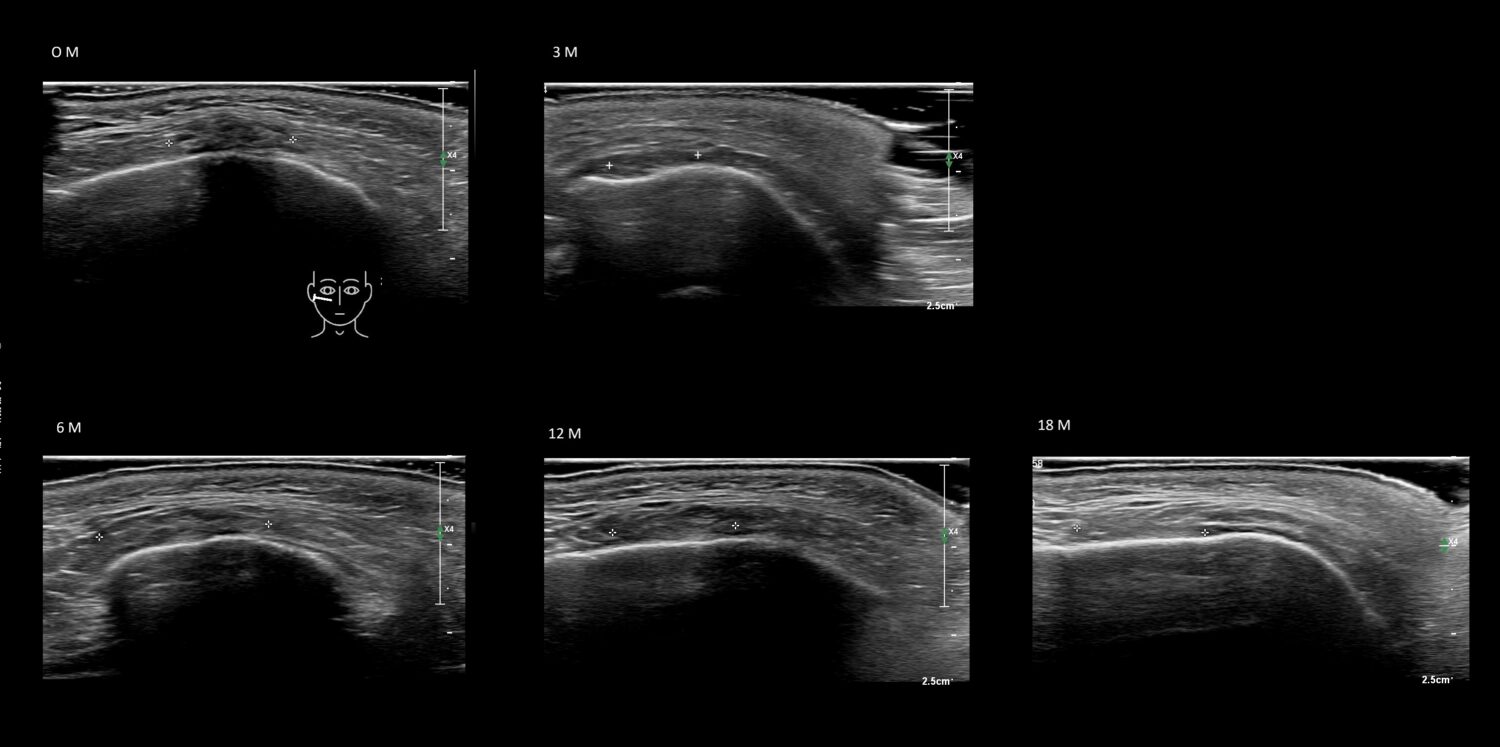

Draw in the image on the right where the fillers are located. To check if your answer is correct, please click on the secondary image.

Draw in the second image below where the fillers are located. To check if your answer is correct, swipe the first image to the right.